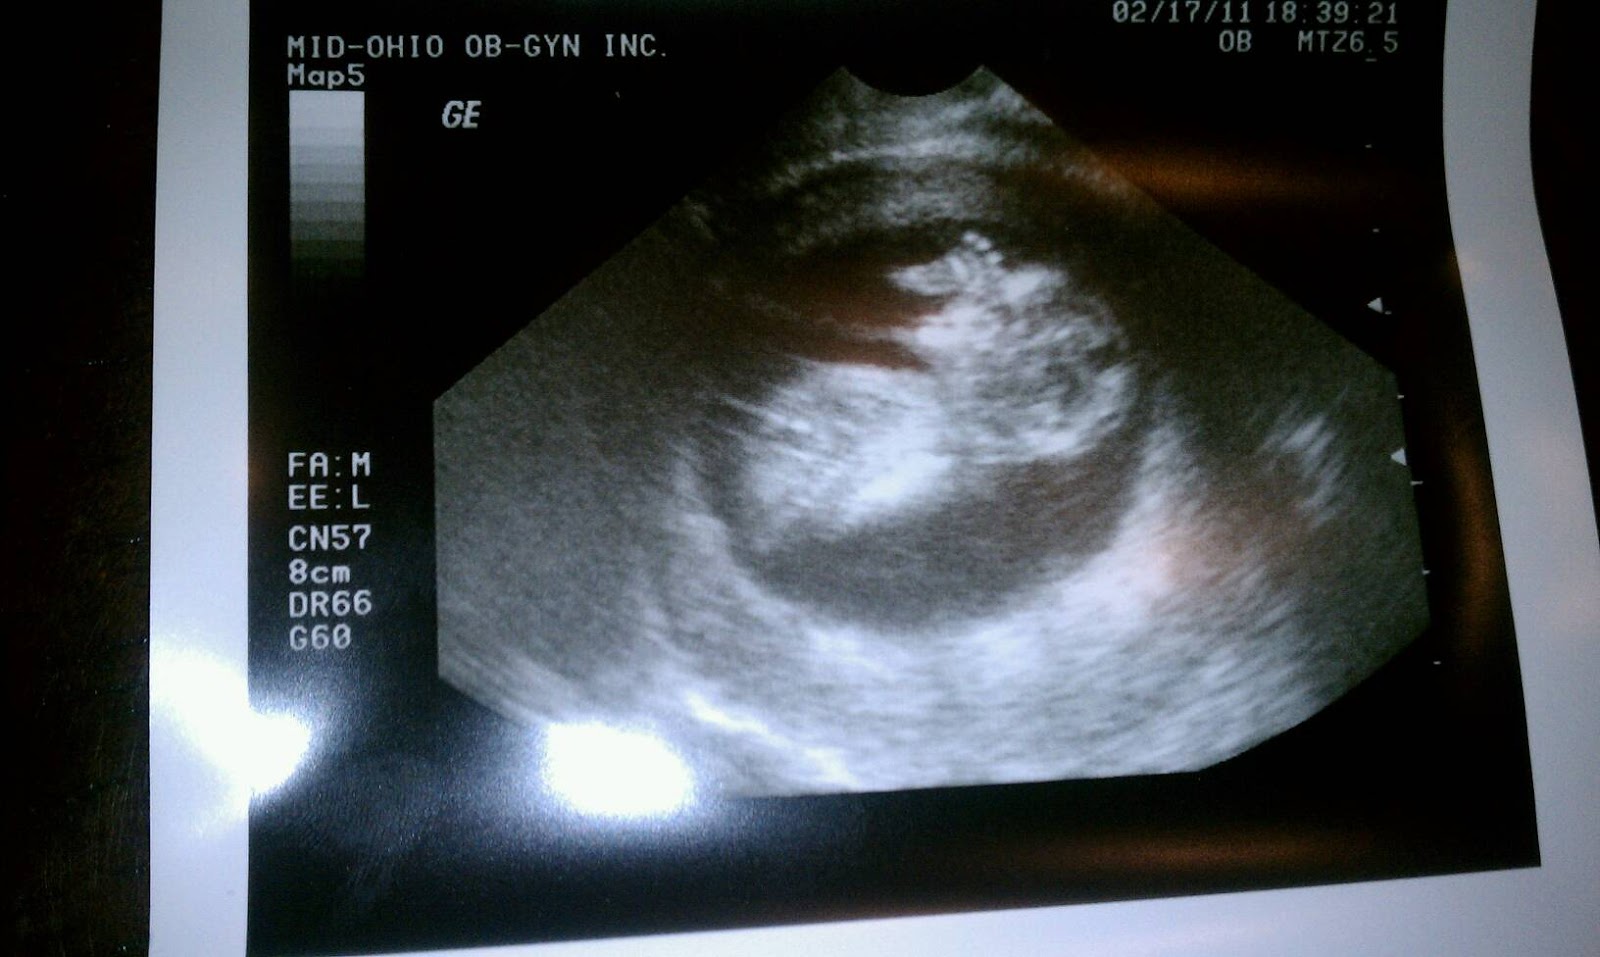

We had our second OB appt today and it was so neat! Dr. Hart asked what we thought the baby looked like last time. I said a bean. Then he showed us the baby just a few weeks later. wow. We could see the brain, hands, legs, bones... it was insane! AND he/she was moving around like crazy. It's so weird that there's all that movement and I can't feel a thing. Oh- second best part was that I only gained half a pound since last visit! Yeay me!